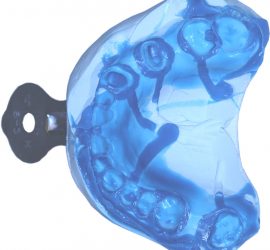

Делятся на механические и функциональные. Ортодонтические аппараты и приспособления делят на аппараты механического и функционального действия. Первые из них (активные) воздействуют на зубы, зубные ряды и их взаимодействие за счет активных элементов — пружин, винтов, резиновой тяги и др.; вторые (пассивные) — действуют во время сокращения жевательных и мимических мышц.